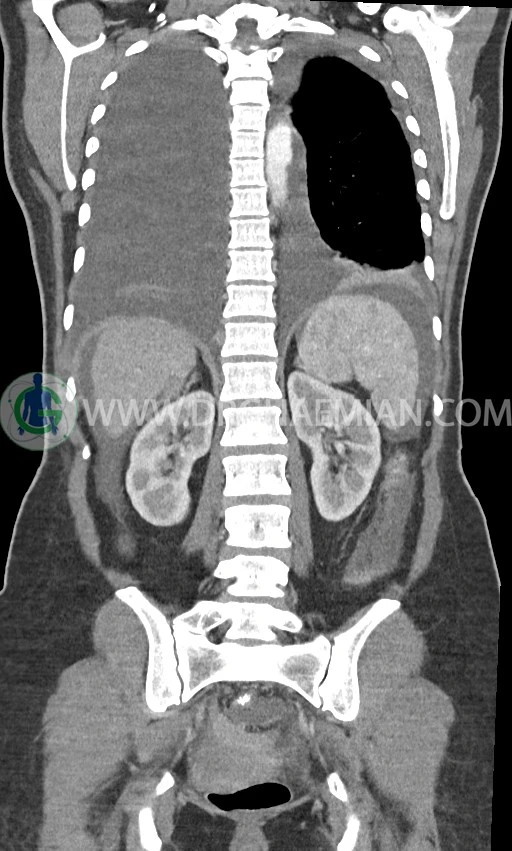

در سی تی اسکن اسپیرال ریه، مدیاستن و شکم و لگن با کنتراست خوراکی و وریدی (مولتی دیدکتور 16 با مقاطع ظریف و بازسازی های ساژیتال و کرونال) :

ضایعه ای در کبد، کیسه صفرا، مجاری صفراوی، طحال، کلیه ها، پانکراس و آدرنالها مشهود نیست.

کلیه ها کنتراست را ترشح کرده اند و نمای سیستم پیلوکالیسیل و حالب دو طرف نرمال است .

توده سالید – سیستیک به ابعاد 40x60mm در تخمدان چپ و به ابعاد 20x40mm در تخمدان راست و

لنفادنوپاتی فراوان در اطراف آئورت و IVC با حداکثر SAD= 25mm در دیواره دو طرف حفره لگن با حداکثر SAD= 20mm

مشهود است.